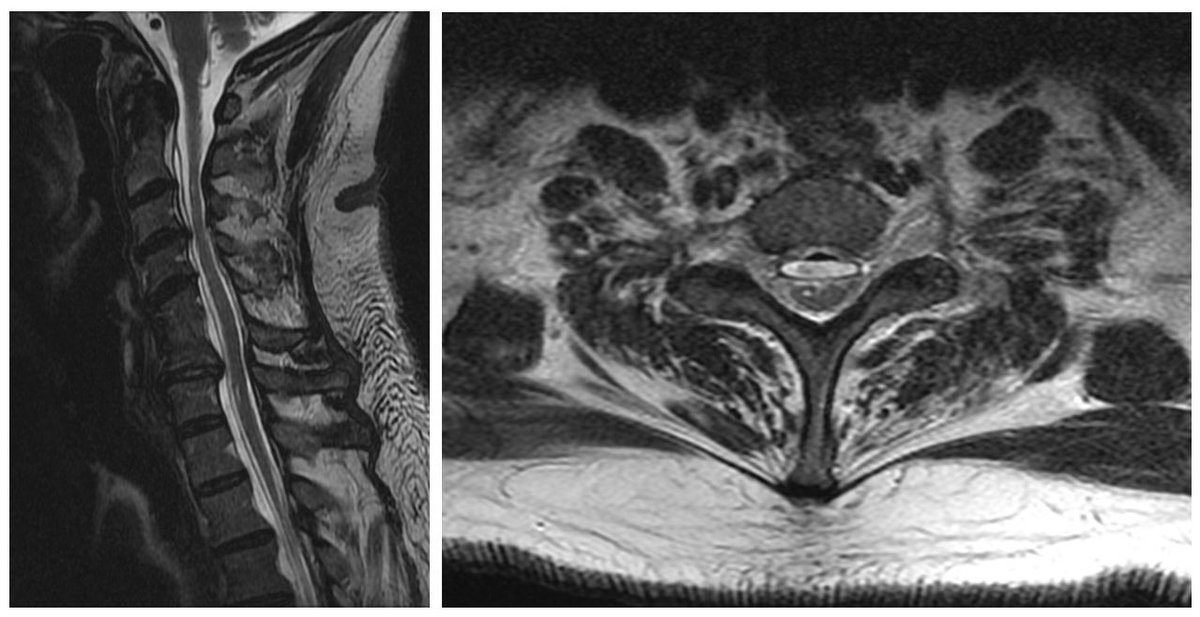

The Case of the Pleasant Surprise: A 52 year old seeks a 3rd opinion for diagnosis of ALS ➡️ Progressive arm weakness over 7 years ➡️ Atrophy and fasciculations in upper limbs only ➡️ Brisk finger flexor and lower limb reflexes MRI has good news. What is it, #neurotwitter?

Lyell Jones MD tweet media